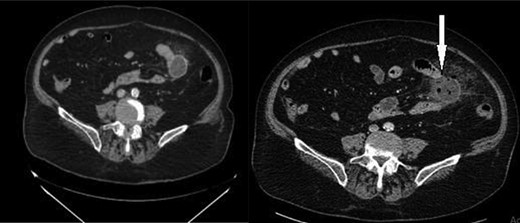

Routine blood tests were done and showed anemia (Hemoglobin 10.9 g/dl) leukocytosis (WBC 15 000/μl) with neutrophil shift (PMN 86%) and an elevated CRP (60 mg/l). Appendicitis was suspected. An enhanced CT scan of the abdomen and pelvis was done and showed a normal appendix, with no evidence of peritoneal free air or fluid. There was a fluid-containing outpouching from the lumen of the proximal small bowel with surrounding mesenteric inflammatory changes, consistent with jejunal diverticulitis (Fig. 5).